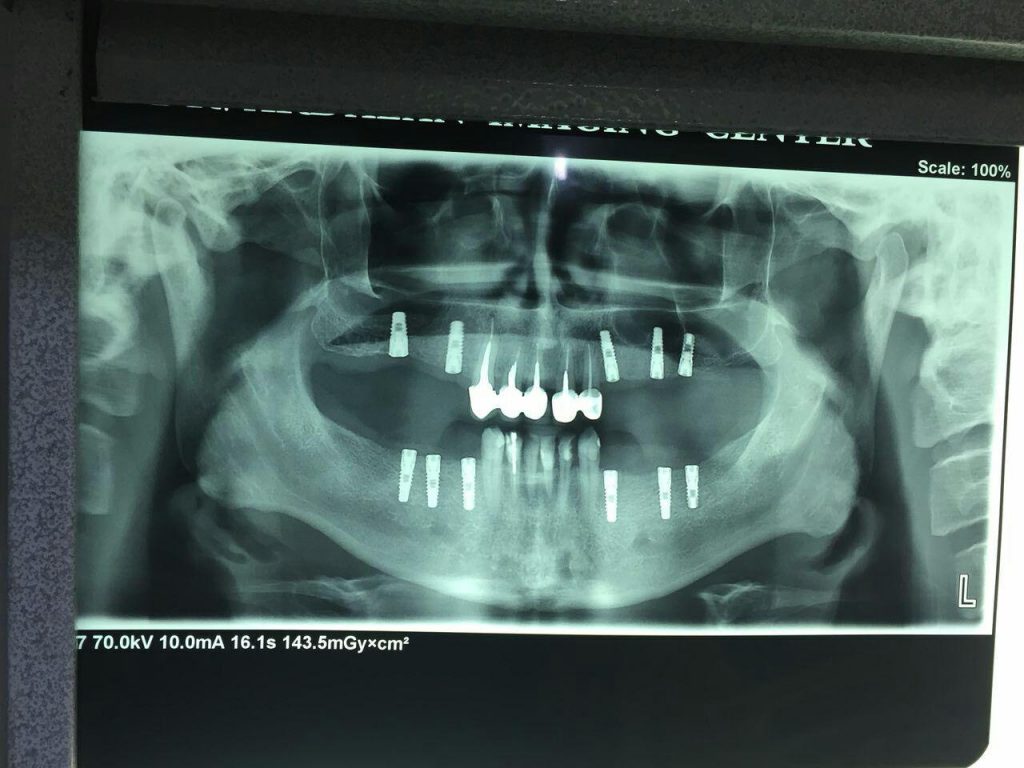

– جراحی های پیشرفته ایمپلنت دندان

جراحی ایمپلنت دندان و گذاشتن پروتز در ناحیه فک و صورت